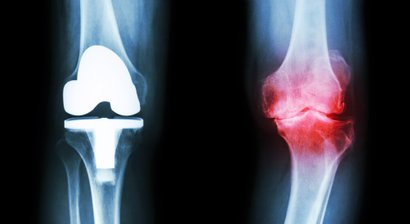

Knieprothese

Für die Behandlung der Kniearthrose stehen, je nach Schweregrad und Beschwerdebild, verschiedene konservative und chirurgische Behandlungsmaßnahmen zur Verfügung (medikamentöse Therapie, Injektionen von Hyaluronsäure/ACP ins Kniegelenk, Physiotherapie, physikalische Therapiemaßnahmen; gelenkerhalten...